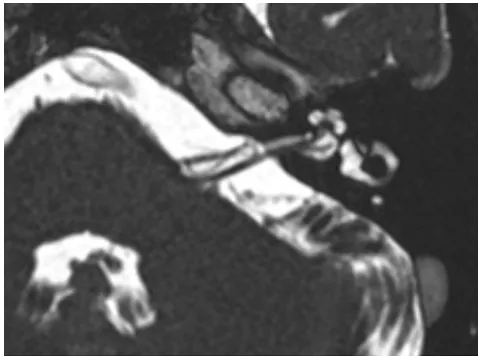

MRI(磁共振):检查发现,在患侧,小脑前下动脉(AICA)的血管袢正压迫着他的前庭耳蜗神经(负责听力和平衡的神经)。

由于患者无法耐受卡马西平的长期服用,他选择接受微血管减压术以求根治。医生通过微创的乙状窦后入路,精准地找到了压迫点,并轻轻的分开被血管压迫的神经,并在二者之间垫入一小块特氟龙垫片,彻底解除了压迫。